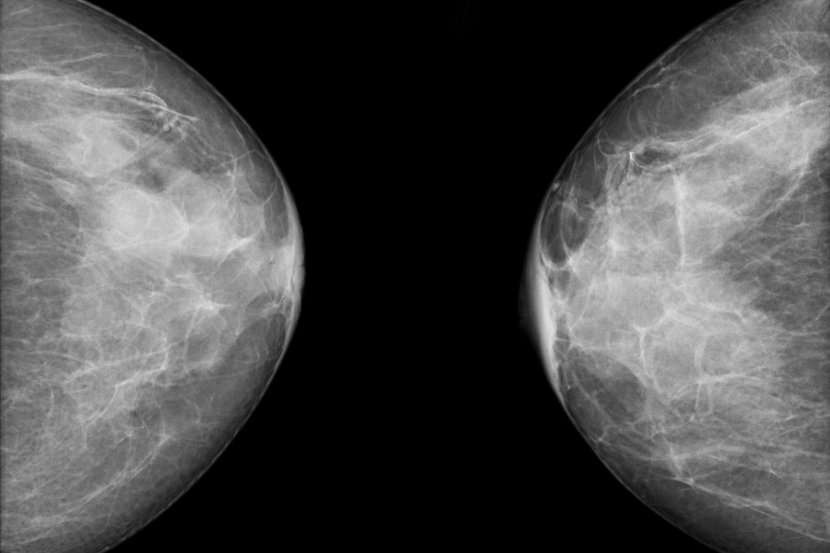

Rizik od raka dojke

Žene sa gustim grudima imaju veće šanse da dobiju rak dojke. Što su grudi gušće, veći je rizik iako naučno još nie dokazano zašto je to tačno. Ali, ističe se da pacijentkinje sa rakom dojke, koje imaju guste grudi, nisu u većem riziku da izgube bitku sa rakom dojke nego žene sa negustim (masnim) dojkama.

Mamografski pregled

Gusto tkivo može da sakrije karcinom dojke. Vlaknasto i žlezdano tkivo na mamografu izgleda belo, baš kao i mogući tumor. Budući da je na mamografu teško napraviti razliku između tumora i gustog tkiva dojke, mali tumor može da se previdi, ne uoči i tako izgubi šansa za početak lečenja na vreme.